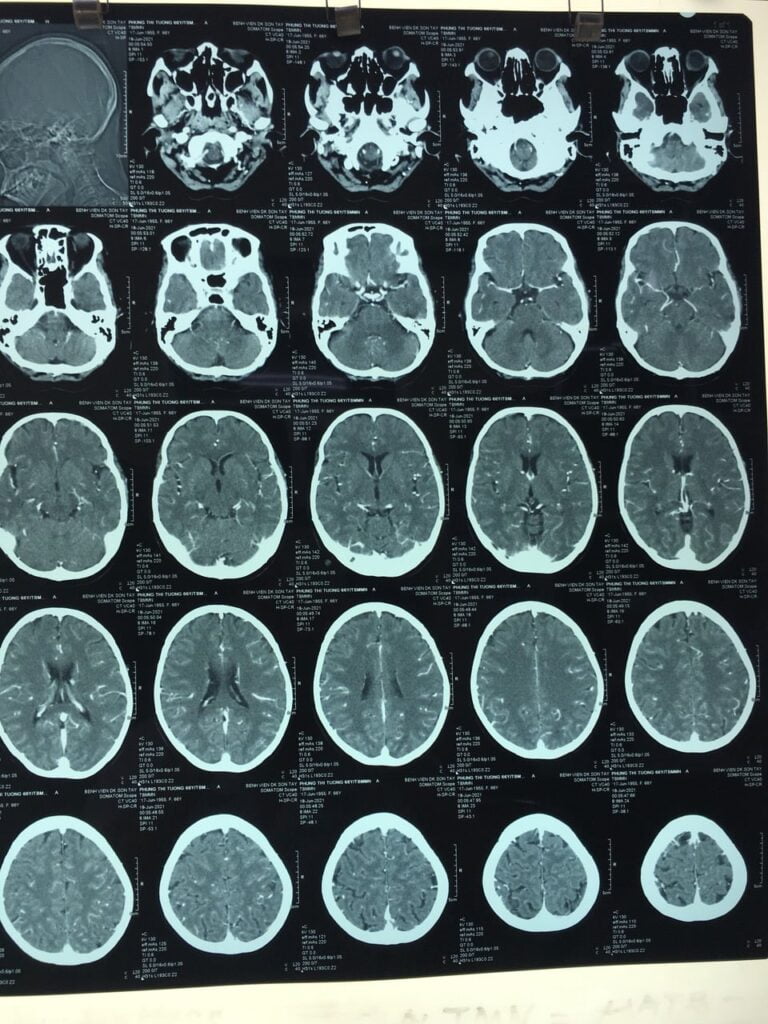

Vừa qua, Bệnh viện đa khoa Sơn Tây đã tiếp nhận bệnh nhân Phùng Thị T, 66 tuổi. Địa chỉ: Sơn Đông, Sơn Tây. Theo người nhà kể lại, bệnh nhân sau khi ăn cơm xong thì đột ngột xuất hiện giảm vận động nửa người bên phải, nói khó, không xử lý gì, vào viện ngay. Tình trạng lúc vào viện, bệnh nhân lú lẫn GCS 10 điểm, liệt ½ người (phải), liệt mặt trung ương. Chụp CT cắt lớp vi tính sọ não, kết quả: Không xuất huyết não, giảm đậm độ thùy đảo (Trái). Xác định bệnh nhân nhồi máu não bán cầu trái, giờ 2.5Tai biến mạch máu não, nhồi máu não, đột quỵ não là bệnh đứng thứ 3 thế giới về tỉ lệ tử vong, là nguyên nhân chính gây tàn phế, di chứng nặng nề, trong đó, nhồi máu não chiếm hơn 80% tổng số các bệnh nhân đột quỵ não. Để điều trị nhồi máu não thành công, vấn đề thời gian và cách thức xử lý có vai trò quyết định. Trước đó, Bệnh viện đa khoa Sơn Tây đã xác định nhiệm vụ phát triển chuyên môn về điều trị đột quỵ não, nhồi máu não bằng phương pháp hiện đại nhất là tiêm thuốc tiêu sợi huyết. Bác sỹ Đào Ngọc Linh – Khoa Hồi sức cấp cứu được lựa chọn cử đi học kỹ thuật này tại Tp Hồ Chí Minh. Sau 3 tháng học tập kỹ thuật, bác sỹ Đào Ngọc Linh đã thực hiện thành công điều trị nhồi máu não bằng phương pháp tiêm thuốc tiêu sợi huyết . Sau 24 giờ gần như mọi chức năng của bệnh nhân Phùng Thị T hoạt động được bình thường, bệnh nhân hết liệt, đi lại được, nói được và hết lú lẫn. Thuốc tiêu sợi huyết rTPA (Alteplase) có vai trò làm tan huyết khối (cục máu đông làm tắc dòng chảy lòng mạch máu não và gây ra đột quỵ não). Huyết khối hình thành được là do fibrin. Trong quá trình ly giải cục huyết khối, plasmin là một chất có tác dụng tiêu hủy firbin tạo thành các sản phẩm thoái hóa có thể hòa tan được. Chất hoạt hóa plasminogen mô tái tổ hợp rTPA (với tên gọi Alteplase) có tác dụng chọn lọc trên fibrin, chuyển plasminogen thành plasmin, làm tan cục huyết khối. Đây là thuốc duy nhất được Hoa Kỳ (cơ quan FDA) chấp thuận sử dụng trong điều trị đột quỵ thiếu máu não cấp trong vòng 3h kể từ khi có triệu chứng đầu tiên xuất hiện. Điều trị bằng thuốc tiêu sợi huyết là biện pháp được khuyến cáo hàng đầu cho bệnh nhân nhồi máu não trong giai đoạn cấp, giúp giảm thiểu tỉ lệ tử vong cũng như di chứng. Theo nghiên cứu NINDS, tỉ lệ hồi phục hoàn toàn khi điều trị bằng Alteplase trong 3h đầu là 38%, tức là cứ 3 bệnh nhân được điều trị, sẽ có 1 bệnh nhân khỏi hoàn toàn. Tỉ lệ tử vong cũng giảm đáng kể khi điều trị bằng Alteplase (16% so với 22%). Các nghiên cứu ECASS III và SITS đã cho thấy, việc mở rộng cửa sổ điều trị lên 4,5h là chấp nhận được. Thời gian được tiêm thuốc càng sớm, tỷ lệ điều trị thành công càng cao. Thuốc tiêu sợi huyết rTPA (Alteplase) làm giảm tỉ lệ tàn tật và tăng khả năng phục hồi vận động của bệnh nhân sau đột quỵ não. Để đạt tác dụng, người bệnh cần được điều trị thuốc tiêu sợi huyết trong vòng 3h kể từ thời điểm xuất hiện triệu chứng. Do đó người bệnh cần được đưa đến bệnh viện càng sớm càng tốt.Đây là kết quả của sự chuẩn bị kỹ càng về chuyên môn kỹ thuật, về trình độ bác sỹ, về trang thiết bị và thuốc, cũng như may mắn của bệnh nhân là nhập viện ngay khi có dấu hiệu đột quỵ, bệnh nhân có được thời gian vàng điều trị. Đánh dấu sự phát triển chuyên môn mạnh mẽ, Bệnh viện đa khoa Sơn Tây đã là một trong những cơ sở đi đầu của các bệnh viện phía Tây thành phố Hà Nội, thực hiện được kỹ thuật sử dụng thuốc tiêu sợi huyết cho những bệnh nhân đột quỵ nhồi máu não giai đoạn cấp. Kỹ thuật tiêm Thuốc tiêu sợi huyết rTPA (Alteplase) làm giảm tỉ lệ tàn tật và tăng khả năng phục hồi vận động của bệnh nhân sau đột quỵ não. Để đạt tác dụng, người bệnh cần được điều trị thuốc tiêu sợi huyết tốt nhất trong vòng 3h, không quá 4 giờ kể từ thời điểm xuất hiện triệu chứng. Do đó người bệnh cần được đưa đến bệnh viện càng sớm càng tốt. Việc lựa chọn đưa bệnh nhân đến những cơ sở điều trị ở xa hoặc chuyển viện có thể làm mất thời gian vàng phục hồi của bệnh nhân, tăng tỉ lệ tàn phế, thậm chí là tử vong.